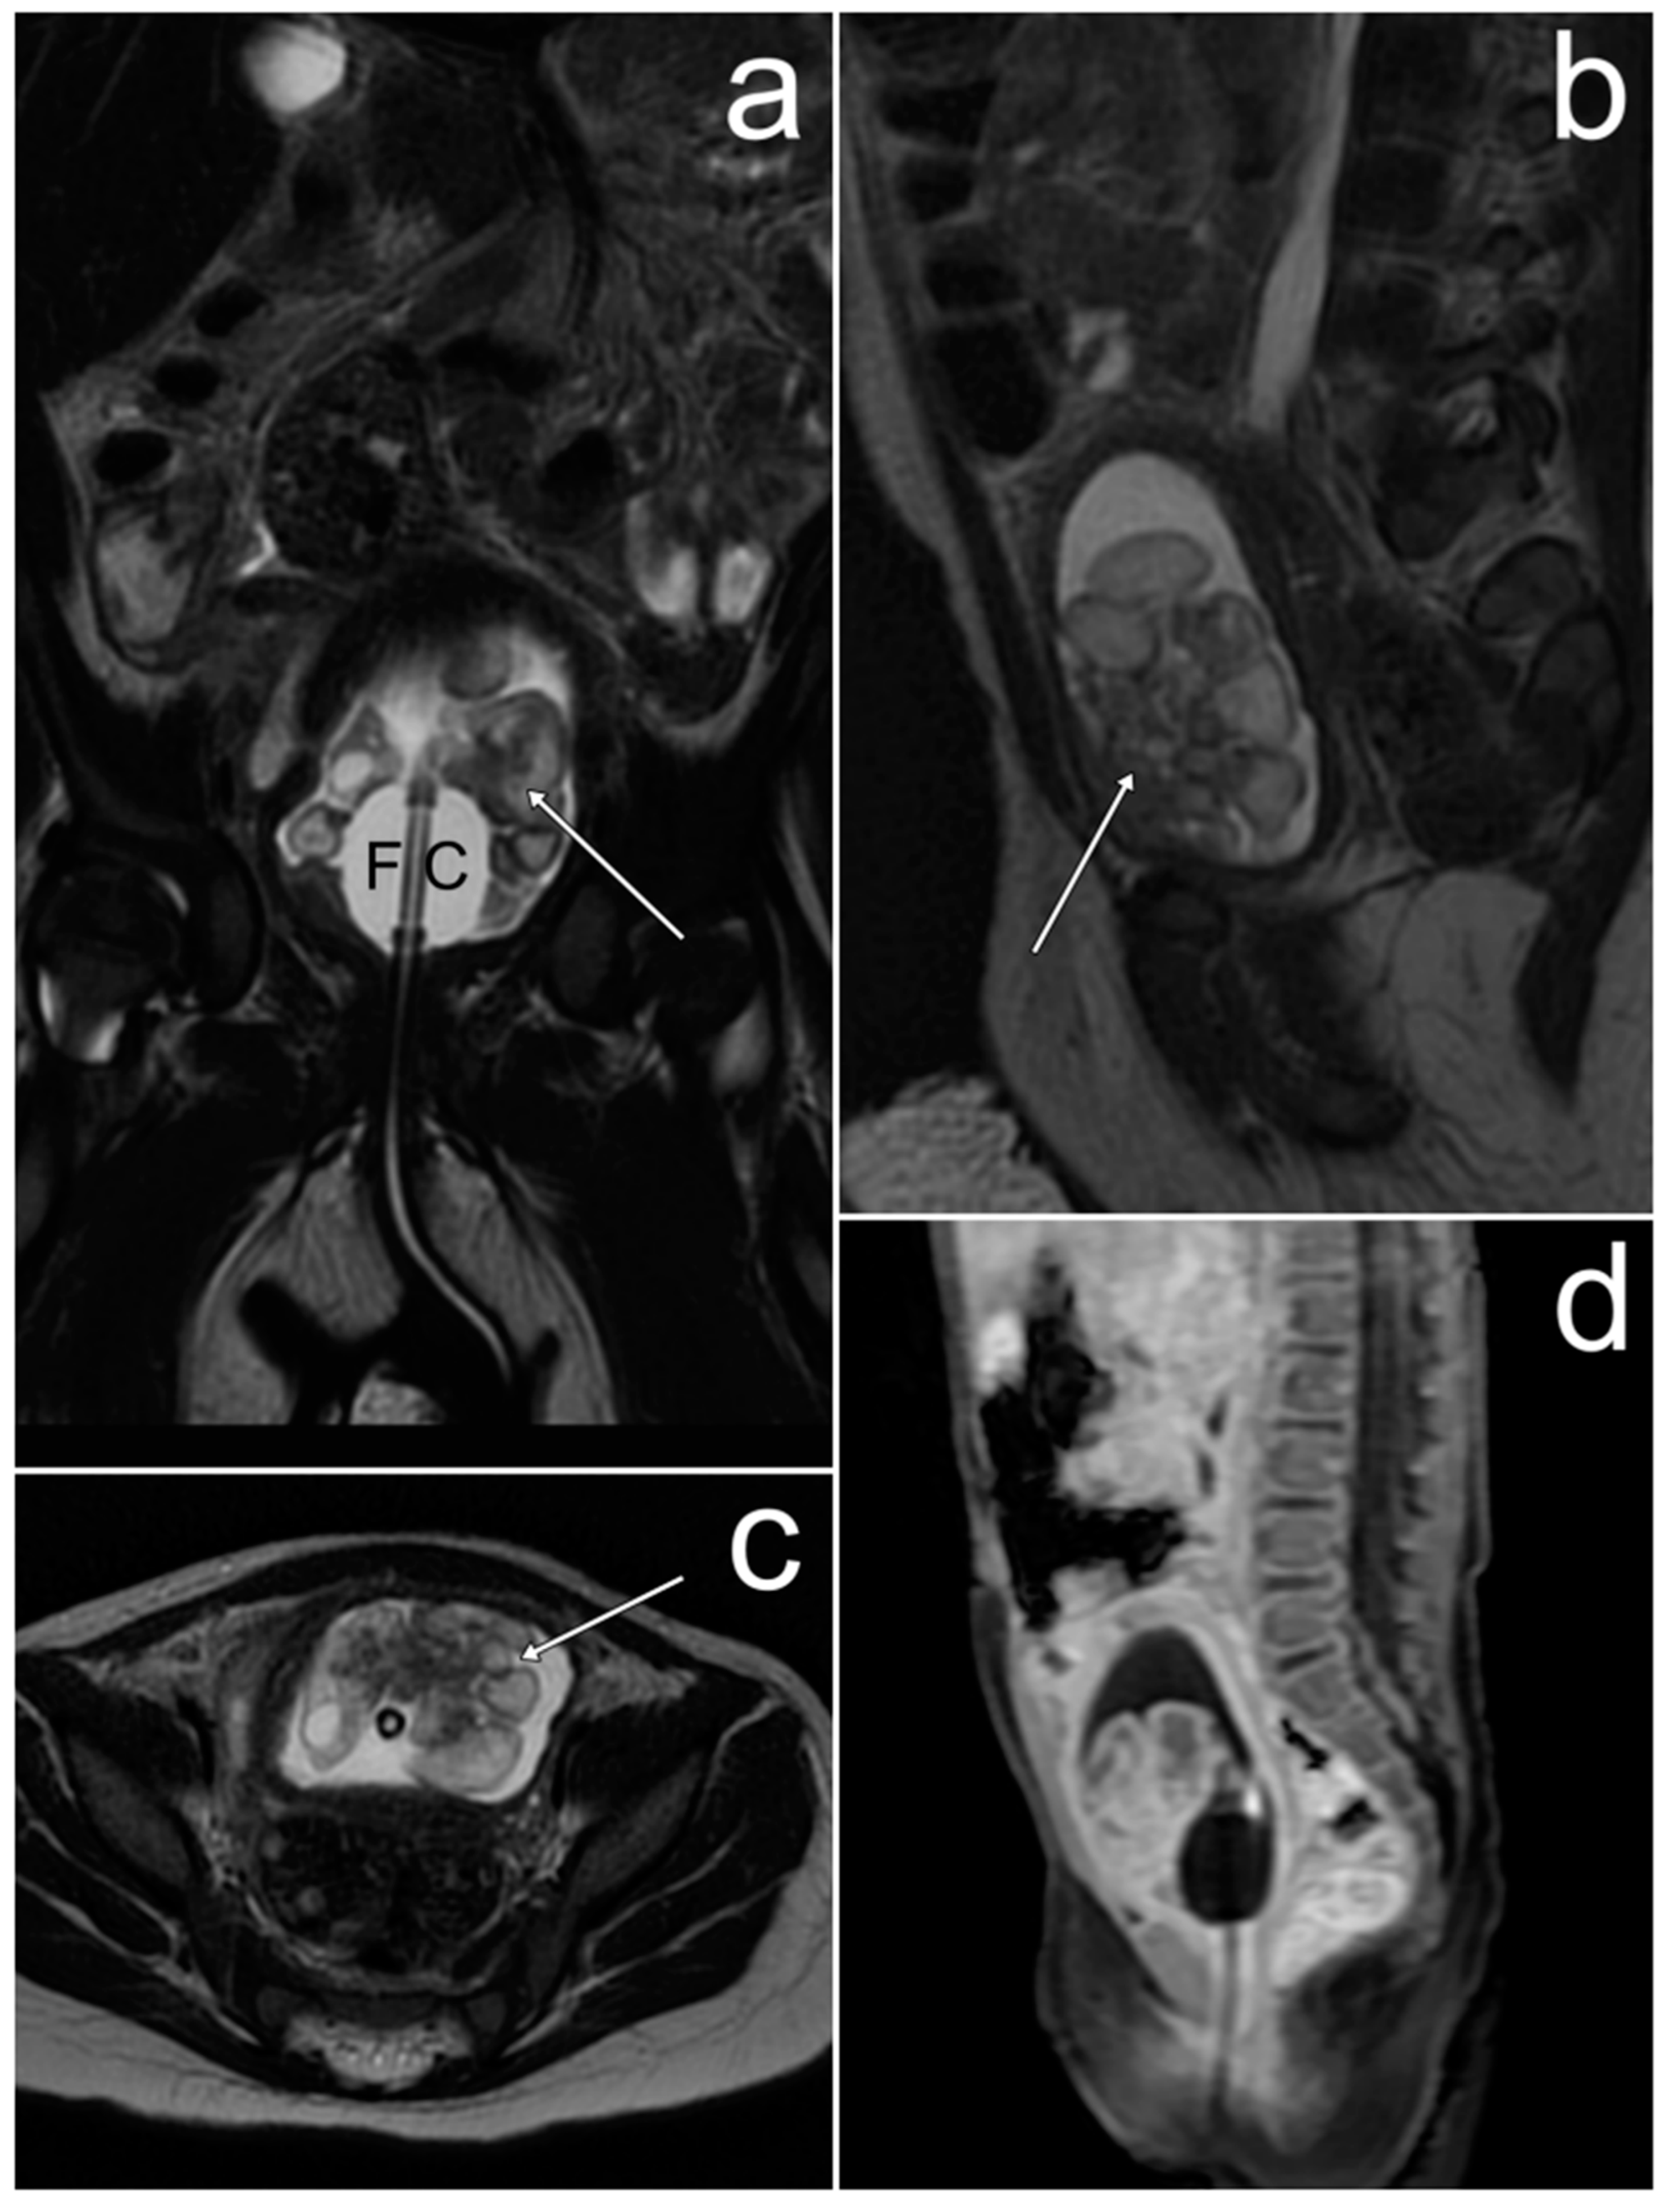

3.3. Diffuse Large B-Cell Lymphoma of the Ovaries

Case Report

| Diffuse large B-cell lymphoma of the ovaries | bilateral, homogenous solid masses; “touching” large ovaries, small cysts arranged linearly around the periphery | elevated Ca-125 andLDH levels | non-specific; pain or discomfort in the abdominal cavity, enlarged abdominal circumference, irregular bleeding, B symptoms (fever, night sweats, or weight loss) |